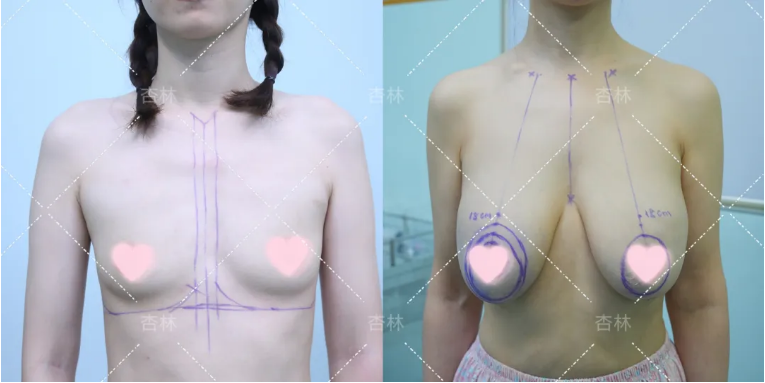

不过好在大家可以选择胸下垂矫正手术,让胸部重新变得挺拔。

然而,有些人在矫正后却发现效果并不理想,没过多久就出现了再次下垂。总之,对于胸下垂矫正,大家都不想花了钱、遭了罪,最后却变成“年抛胸”。

图片来源于网络